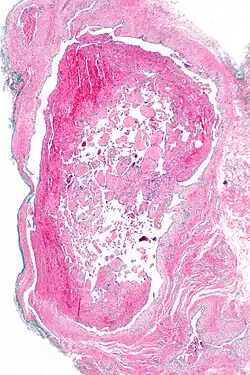

| Micrograph of intravascular papillary endothelial hyperplasia. H&E stain. | |

Immunohistochemistry staining in addition to a thorough histomorphological evaluation are necessary for a correct diagnosis.[10] A crucial tool for diagnosing it is microscopy. IPEH is made up of an intravascular proliferation of many papillae with an endothelial surface and a connective tissue core.[11] It differs from other neoplastic lesions in that it is often encapsulated or well-circumscribed, displaying distinctive papillary fronds, and the vascular wall completely restricts the proliferative process.[12]